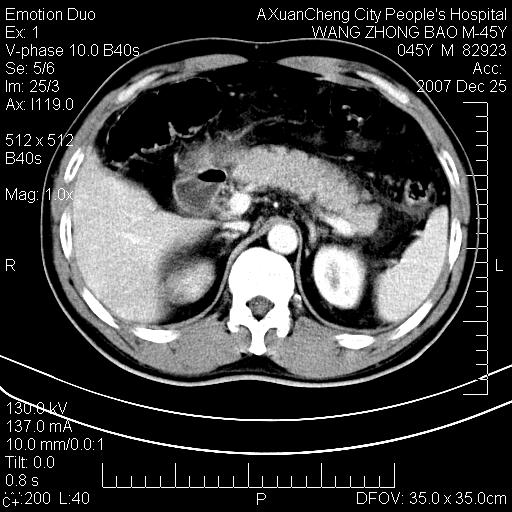

以下是引用卜一在2007-12-25 14:07:00的发言:[br]胰头钩部略增大,与十二指肠壶腹部关系密切,其内明显见软组织密度肿块,明显强化,但肠壁较光滑 柔软。考虑:炎性增生!建议消炎后复查!待除外壶腹部腺癌!

以下是引用zjzjr在2007-12-25 13:35:00的发言:[br]考虑正常的十二指肠乳头部,建议胃镜检查.

以下是引用qiuleiyu在2007-12-25 18:14:00的发言:[br]胰腺增大,周边渗出改变,肾前筋膜明显增厚,示少量积液.胆囊壁毛糙,周边少许渗出,胆总管壁厚,异常强化,然扩张不明显.结合病程急短;考虑;胆管炎,胆囊炎,胆源性胰腺炎可能大,请结合实验室检查及随访.

以下是引用lisihao在2007-12-25 14:23:00的发言:[br]急性水肿型胰腺炎[br]依据:1、胰腺弥漫性肿大,边缘稍毛糙;[br] 2、双侧肾周筋膜增厚,尤以左侧为甚(重要征象)[br] 3、双侧后胸膜增厚(刺激性炎症);[br] 4、结合病史,查血尿淀粉酶应该可以确诊。